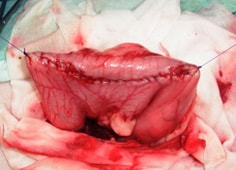

子宮蓄膿症

子宮蓄膿症とは、子宮の中に膿がたまり、放っておくと子宮が破裂したり、子宮内の菌が全身に蔓延してしまう、死に至る緊急性の高い病気です。

早急に外科的摘出が望まれます。

![]() 摘出された子宮蓄膿症の卵巣子宮 |